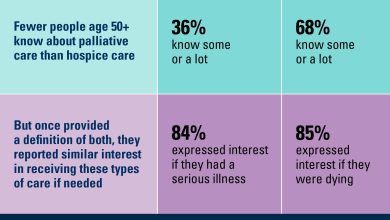

Pesquisa sobre cuidados paliativos e hospice revela grandes lacunas

Resultados da Pesquisa Nacional sobre Envelhecimento Saudável sobre a consciência e o interesse em cuidados paliativos e hospícios entre adultos…

Ler Mais »